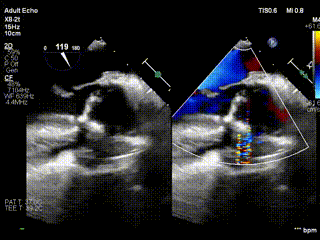

视频5:病例3术前大量主动脉瓣反流

视频6:病例3术后未见反流